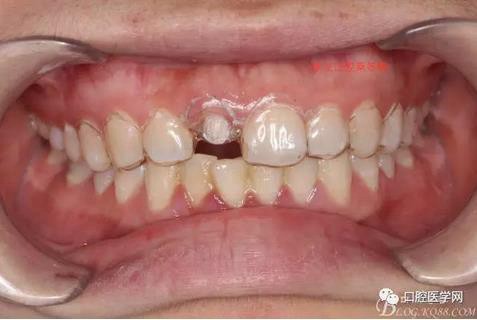

術(shù)前口內(nèi)照,11殘根,唇側(cè)牙齦紅腫,肩臺在齦下2毫米,舌側(cè)正常.21有被動萌出,長寬比例不協(xié)調(diào)。口腔衛(wèi)生一般,有菌斑。

術(shù)前原有牙冠復(fù)位,牙齦紅腫。